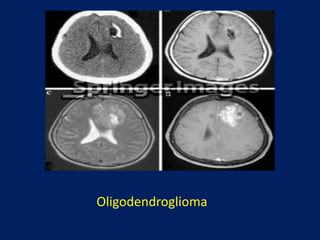

oligodendroglioma